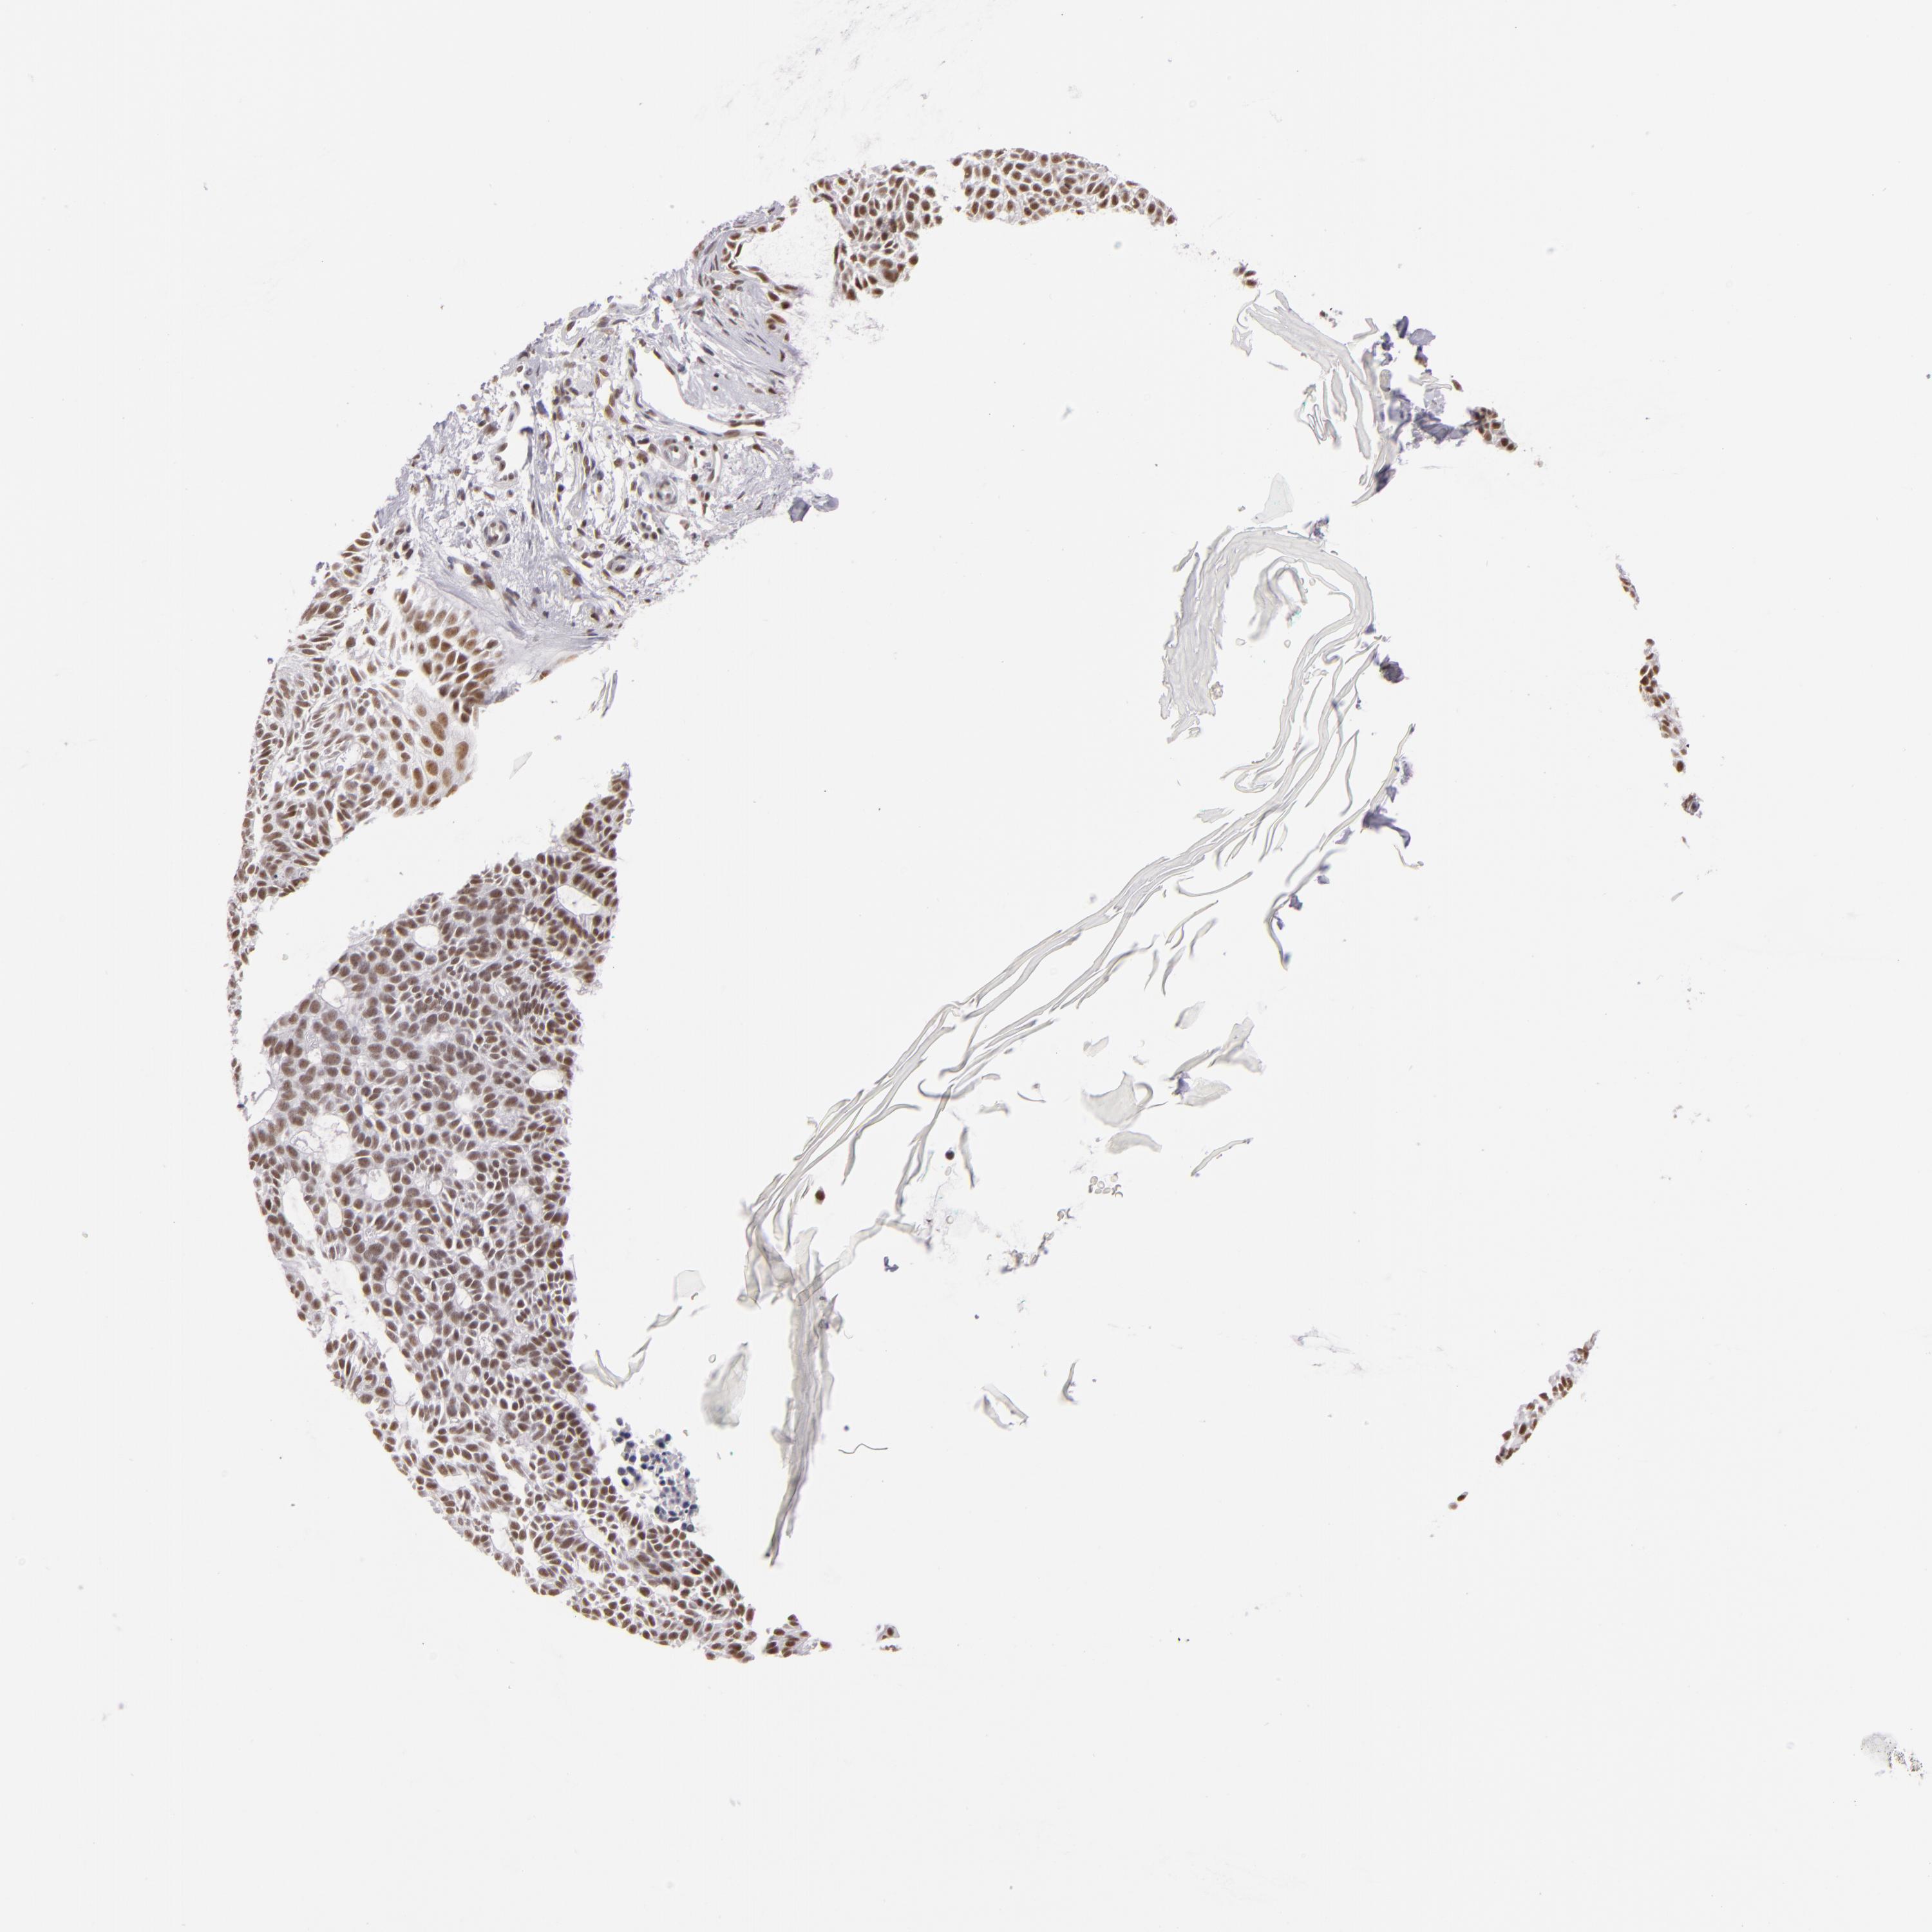

SKIN CANCER - Protein expressioni

A mouse-over function shows sample information and annotation data. Click on an image to view it in a full screen mode. Samples can be filtered based on level of antibody staining by selecting one or several of the following categories: high, medium, low and not detected. The assay and annotation is described here.

Antibody stainingi

Antibody staining in the annotated cell types in the current human tissue is reported as not detected, low, medium, or high, based on conventional immunohistochemistry profiling in selected tissues. This score is based on the combination of the staining intensity and fraction of stained cells.

Each image is clickable and will lead to virtual microscopy that enables deeper exploration of all samples and also displays staining intensity scores, fraction scores and subcellular localization as well as patient and tissue information for each sample.

Antibody HPA001552

Staining

High

Medium

Low

Not detected

Intensity

Strong

Moderate

Weak

Negative

Quantity

>75%

75%-25%

<25%

None

Location

Nuclear

Cytoplasmic/membranous

Cytoplasmic/membranous,nuclear

Squamous cell carcinoma, NOS